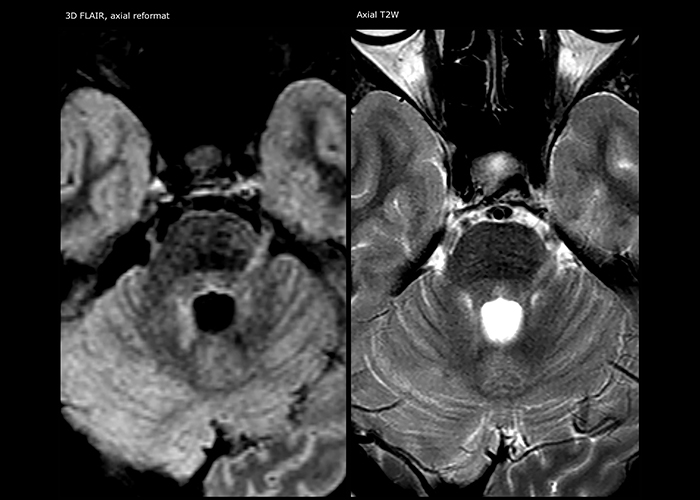

Multiple sclerosis imaging requires precision, speed

When multiple sclerosis (MS) is suspected, clinicians need a diagnosis early on, so treatment can begin as soon as possible. “A challenge for imaging is that MS lesions in the brain and spine may be very small,” says Dr. Savatovsky. “We need precise imaging to tell exactly where the lesion is, so we need high quality, very high resolution images, preferably in 3D[1]. We need to know if a high T2 signal intensity is suggestive of MS or just aspecific. And we want to visualize active lesions very well.”

“Ingenia 3.0T provides us very good image quality with high SNR, even if we push the resolution. For example, in FLAIR images we may have an isotropic resolution of 0.9 mm. Ingenia allows us to use 3D T1 TSE with BrainView, which has a better sensitivity than 2D spin echo imaging[2] and 3D gradient echo imaging. Ingenia also provides highly reproducible exams, which is important in MS imaging so that follow-up exams at different time points are done the same way.”

Imaging MS in brain

For MS imaging in the brain, Dr. Savatovsky uses 3D FLAIR as the basic sequence to visualize the lesions and assess the situation and lesion load. “We count the lesions in each location to determine if the criteria of the disease are fulfilled. We use a T2-weighted sequence because our neurologists are used to it. We compare the lesion load on FLAIR with a 3D T1 post-contrast sequence to help us determine whether lesions are old or new. We typically administer the contrast before the patient enters the machine because it shortens the examination time and allows to visualize active lesions that tend to be more visible after several minutes. When a differential diagnosis is difficult, we add sequences such as susceptibility imaging, because some focal MS lesions have a small vein in the center[3].”